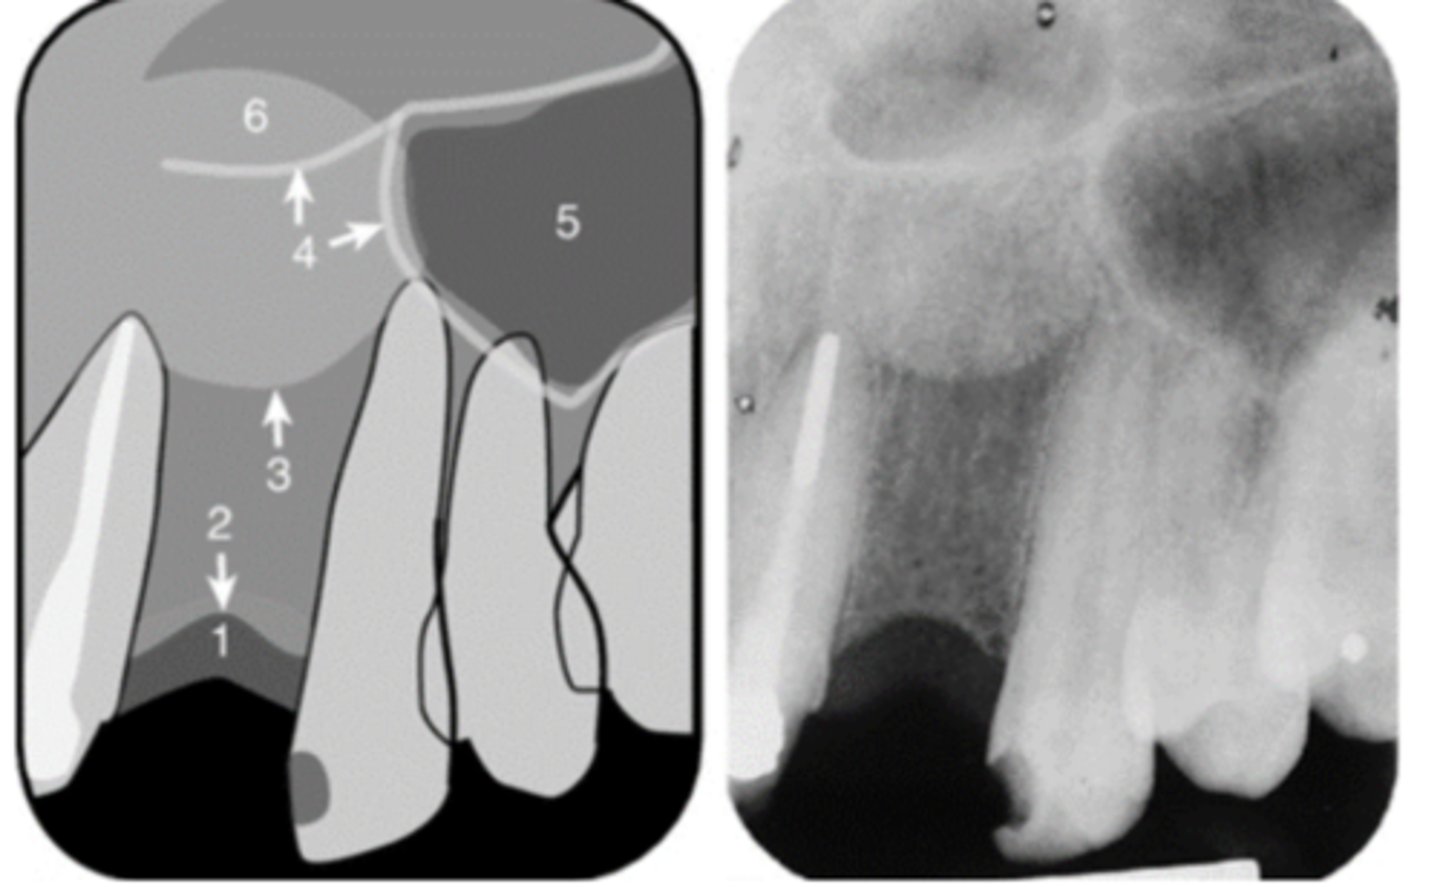

Floor of maxillary sinus

Name the curved, radiopaque line that superimposes the roots of the teeth indicated by #7.

<p>Name the curved, radiopaque line that superimposes the roots of the teeth indicated by #7.</p>

Floor of the maxillary sinus

Name the line indicated by arrows labeled #2.

<p>Name the line indicated by arrows labeled #2.</p>

Zygoma

Name the horizontal radiopaque line labeled #2.

<p>Name the horizontal radiopaque line labeled #2.</p>

Name the curved line scalloping between tooth roots labeled #3.

<p>Name the curved line scalloping between tooth roots labeled #3.</p>

Inverted Y

Name the two thin, curved, radiopaque lines that merge indicated by arrows #4.

<p>Name the two thin, curved, radiopaque lines that merge indicated by arrows #4.</p>